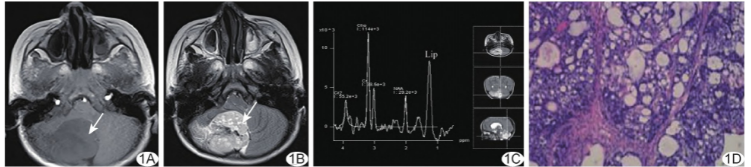

3天;既往无特殊病史及家族史。查体未见明显异常。实验室检查:血清甲胎蛋白(alpha-fetoprotein,AFP)2 664 ng/ml。颅脑MRI:右侧小脑半球37 mm×39 mm×35 mm T1WI等-稍低信号占位,边界清晰(图1A),T2WI呈高信号内见条片状混杂低信号及多发小灶样更高信号(图1B),弥散加权成像(diffusion weighted imaging,DWI)呈等信号,表观弥散系数图呈稍高信号;周围见斑片状水肿

,小脑蚓部及小脑扁桃体受压向前或前上移位,第四脑室受压变形、出口闭塞,幕上脑室系统扩张;增强后病变明显强化,内见条片状及灶状无强化。

1H-MR波谱(MR spectroscopy,MRS):病变区N-乙酰天冬氨酸(N-acetyl aspartate,NAA)峰明显减低,胆碱(choline,Cho)峰明显升高,可见高耸脂质(lipid,Lip)峰(图1C)。MRI诊断:右侧小脑半球占位,室管膜瘤可能性大。

术后病理:光镜下见扁平、立方形肿瘤细胞,细胞质稍透明,核仁明显,可见核分裂,腔内见透明小体及基底膜样物质沉积,含内胚层、网状、微囊状、乳头状及实性结构(图1D);免疫组织化学:AE1/AE3(+),SALL4(+),Glypican-3(+),CK8/18(+),CD117(+),AFP(+),HNF1β(+),Ki-67(67%+),CEA(-),EMA(-),PLAP(-),HCG-β(-)。病理诊断:(右侧小脑)内胚窦瘤。本例报道经医院伦理委员会批准(2019-KY-231)。

图1 右侧小脑内胚窦瘤。A、B.颅脑轴位MR T1WI(A)及T2WI(B);C.1H-MRS图;D.病理图(HE,×200)(箭示病灶)